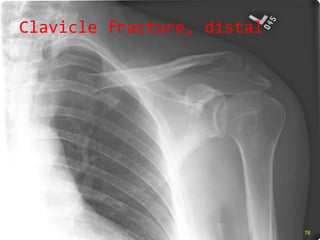

Clavicle fracture, distal